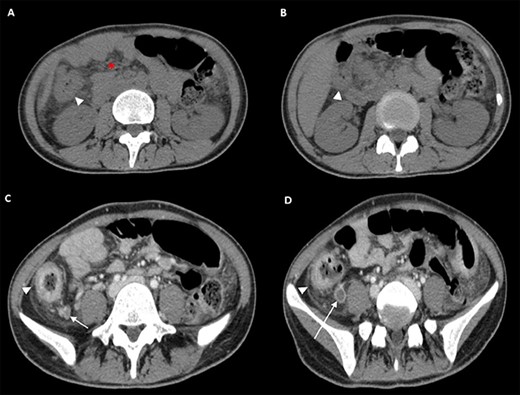

The following tests were carried out in ER: swab for severe acute respiratory syndrome coronavirus 2 (SARS-CoV2; negative), electrocardiogram, blood tests showing normocytic anemia, without leukocytosis, mild lymphocytopenia, and elevated C-reactive protein (CRP, 47 mg/L), chest X-ray (negative). Contrast-enhanced computed tomography (CT) showed increased densification of adipose tissue along the whole colon, the cecum and part of the ascendant had thickened walls (Fig. 1, panel A and B) with enhancement of the mucosa and submucosa edema, locoregional lymphoglandular large ~2 cm also partially colliquate (Fig. 1, panel C and D); lumen narrowing and strictures along the preterminal ileum and ascites. A colonscopy was performed, which revealed a patulous ileocecal valve, a bowel that was completely subverted from the cecum to the hepatic flexure with multiple and extensive deep fibrin-coated ulcers; the residual mucosa appeared pink with multiple pseudopolipoid protrusions (Fig. 2). Tests for HIV, HCV, stool cultures, parasitological and Clostridium difficile toxin were all negative and she was immune to hepatitis B virus. Quantiferon-test still outstanding.

Colonoscopy. Digital photograph from optical colonoscopy shows the endoscopic capture of suffering and ischemic mucosa with deep fibrin-coated ulcers.